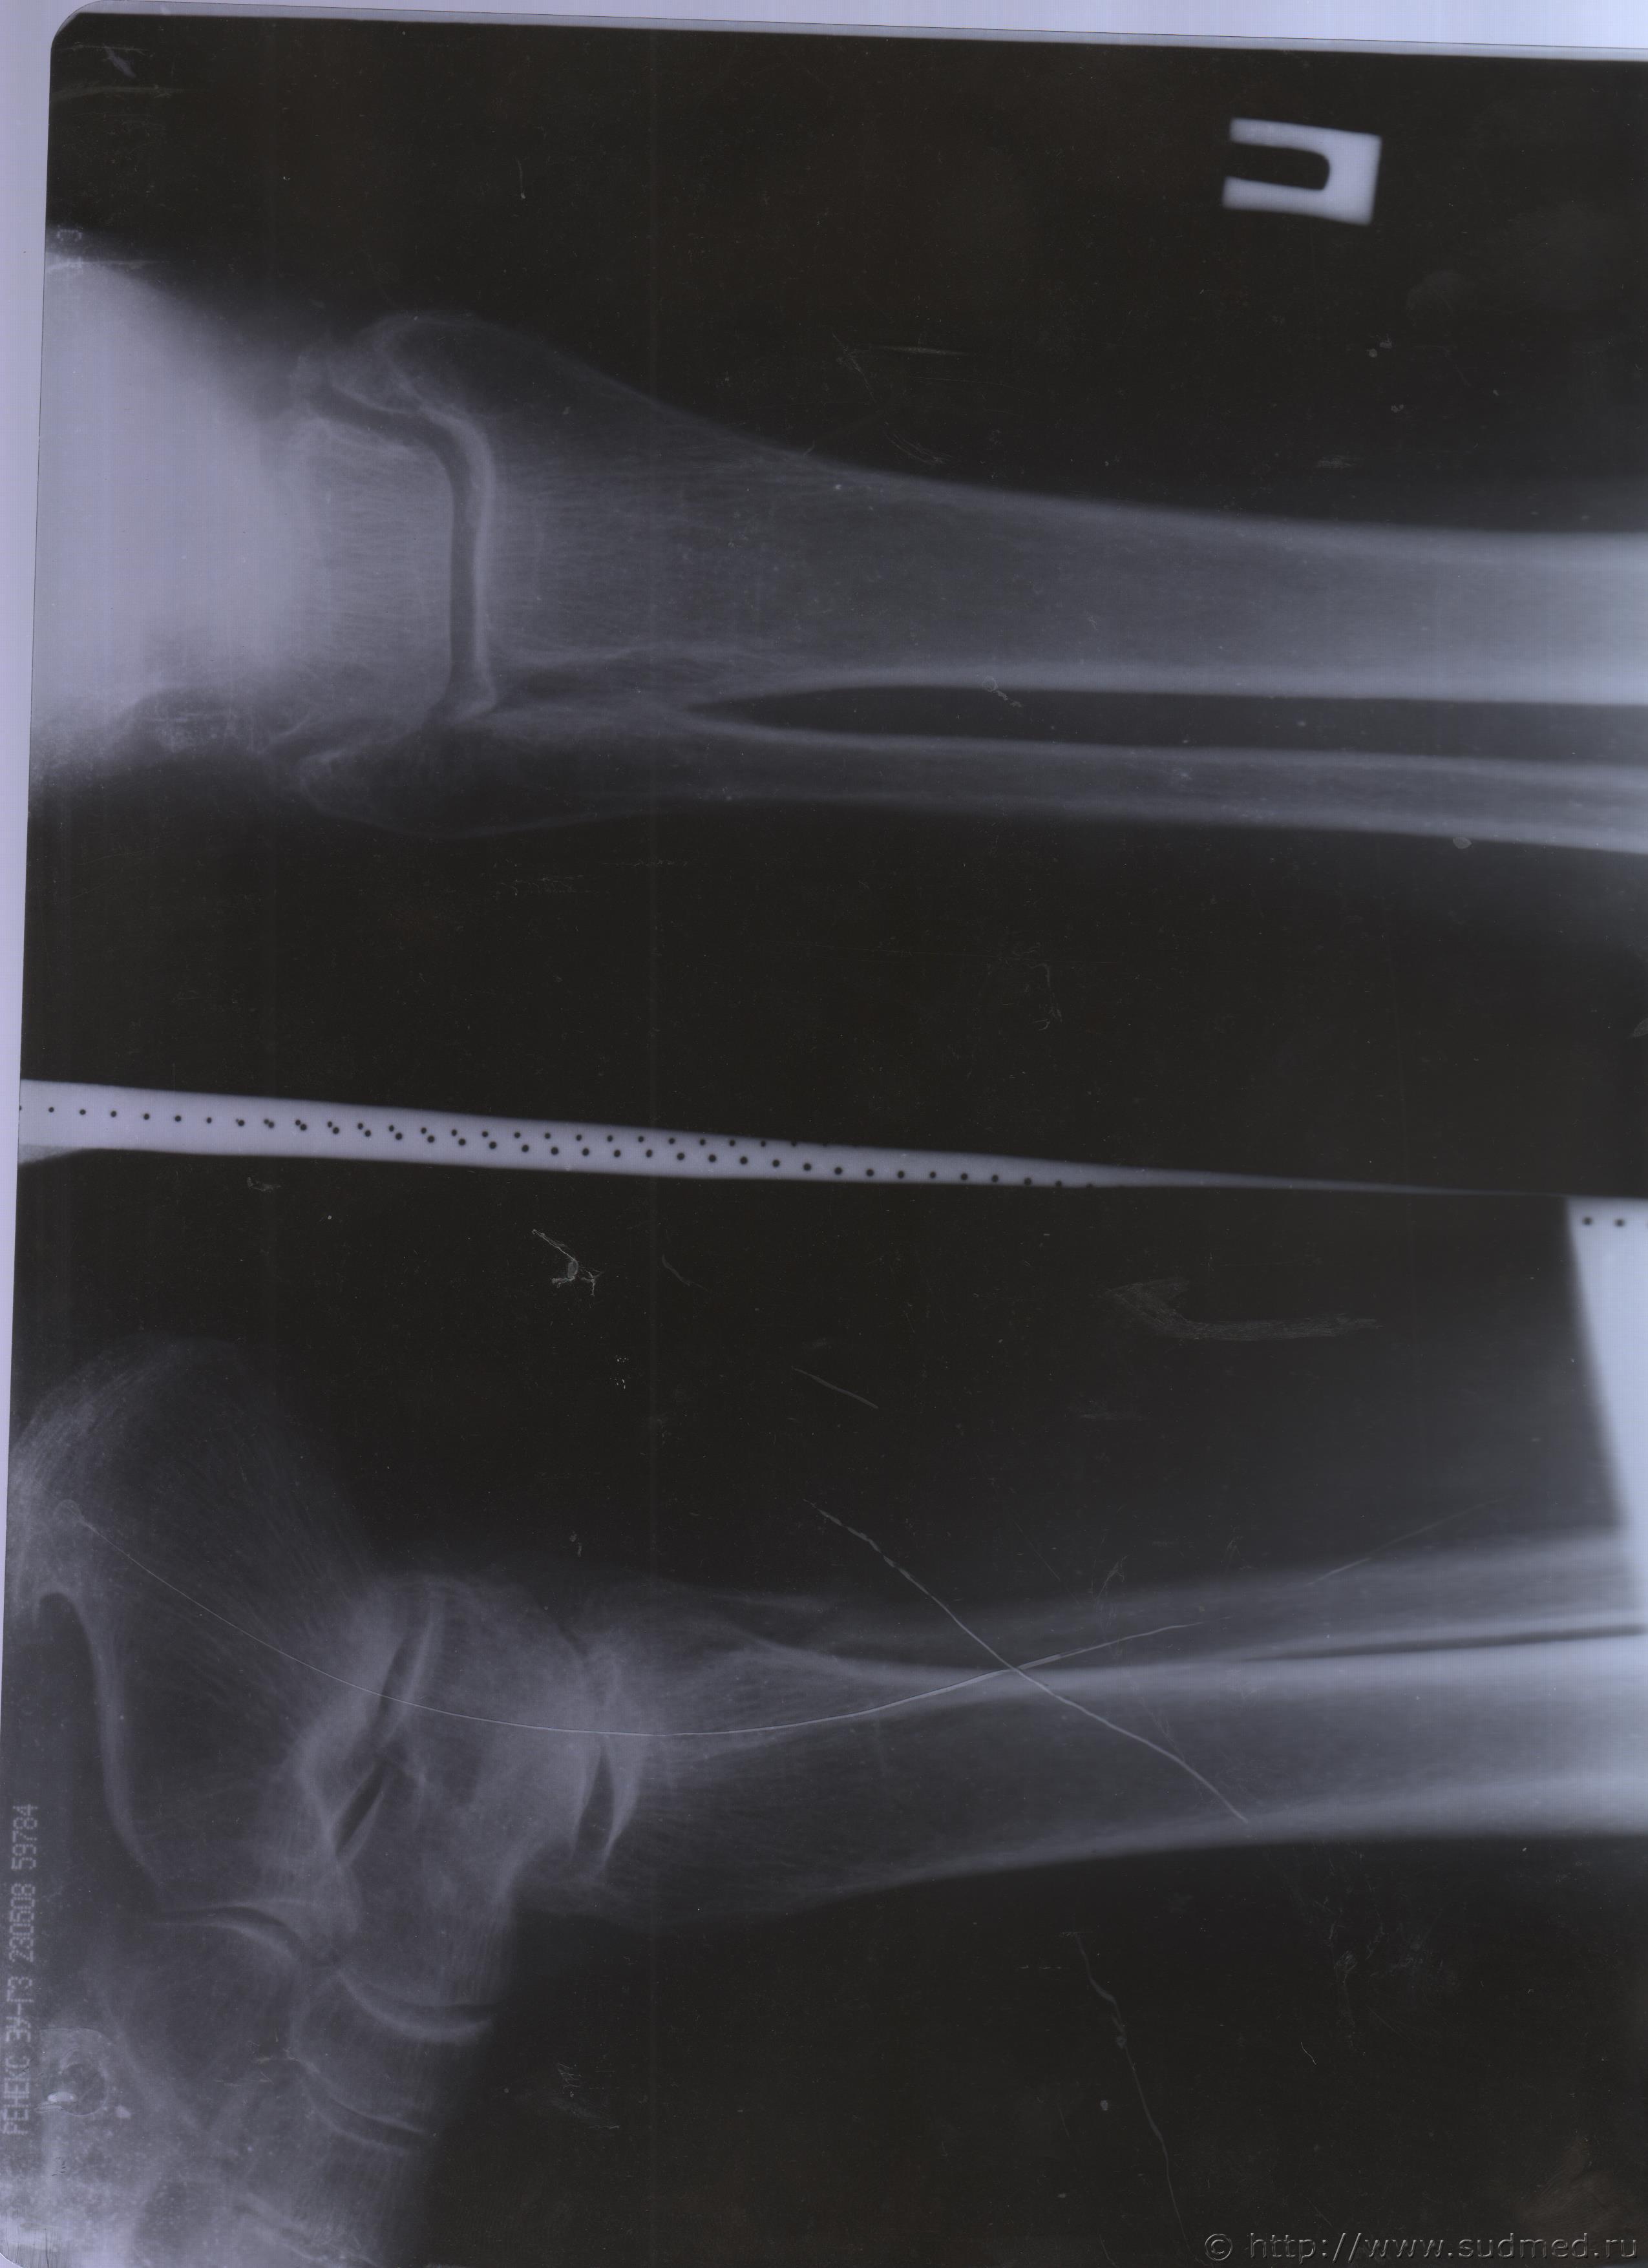

06.07.2015 г. при обращении в горбольницу мне выдали не описанный снимок( все рентгенологи были в отпуске) и справку № 4379 от 06.07.15 г. где диагноз: закрытый 2-х лодыжечный перелом правой голени без смещения. Копию справки прилагаю

За все 12 месяцев, что была на больничном, 8 раз делали снимки травмированной ноги и все заключения именно : «закрытый 2-х лодыжечный перелом правой голени без смещения».

После того, как был поставлен диагноз : «компрессионный перелом L2 позвонка поясничного отдела позвоночника». Амбулаторная мед карта, была украдена из кабинета врача травматолога. При восстановлении мед карты( в марте 2016 г.), врачом травматологом была взята копия справки от 06.07.15 г.из приемного отделения горбольницы. Справка № 4379 ( дубликат), диагноз : «закрытый 2-х лодыжечный перелом правой голени без смещения».

Уважаемые доктора, нужны ли снимки по перелому правой голени? и Заключения по МРТ и КТ.Ранее представляла результаты обследования...Сделала копию снимков по КТ и МРТ( только вот какого качества получились не знаю.)

Посмотрите, пожалуйста

Посмотрите, это снимки за 12 месяцев.

Уважаемая Татьяна! По представленным Вами снимкам ничего сказать нельзя: нет маркировки даты каждого снимка (поэтому, невозможно их сравнивать друг с другом и соотносить с датой травмы), исследование непосредственно пленок гораздо более информативно, чем анализ представленных изображений (детали костной структуры в зоне перелома практически не видны).

Рекомендую проконсультировать все эти снимки у высококвалифицированного рентгенолога. Далее - по ситуации, т.е. в зависимости от его мнения. В любом случае, есть формальные основания для назначения дополнительной экспертизы, т.к., судя по представленному Вами фрагменту заключения эксперта, на экспертизу не были предоставлены все мед.документы с данными о лечении предъявляемой травмы (Вы пишете, что рентгенограммы делались на протяжении 12 месяцев, полагаю, что Вы и врачами наблюдались в течение этого срока, т.е. велась мед.карта).